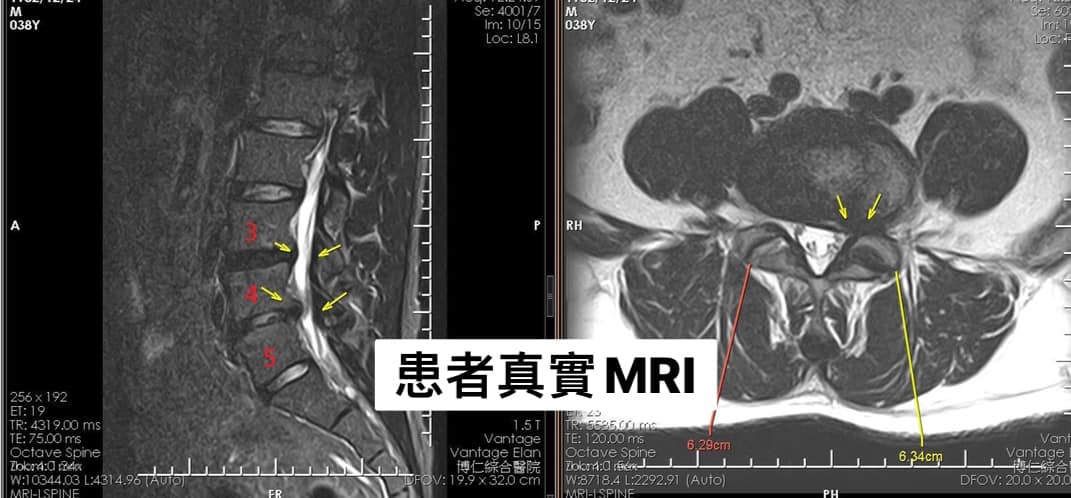

Cervical Spine Treatment Cases 腰椎治療案例 #巨大椎間盤突出一定要開刀嗎? #兩家醫學中心外科醫師說很嚴重! #有沒有辦法逆轉勝... 2021.08.10 ❖ 椎間盤突出治療醫案 ❖晨起痛爆整個人無法工作心情沮喪 😂骨科醫師說復健如果沒效可... 2022.05.12 #天才年輕賽車手巨大椎間盤突出醫案 #八周治療完全逆轉勝康復 #重新回到合法賽車場競... 2021.07.20 #腰椎滑脫痛苦不堪 #右腳麻痛無法彎腰刷牙 #感謝桃園市楊小姐熱情見證 #患者親自贈送... 2021.06.15 #巨大椎間盤突出醫案 #真的逆轉勝超感動 #三個月治療完全徹底改善 #脊刻救援成功 #徹... 2021.06.12 ⭕️L4L5巨大椎間盤突出治療醫案 🌟八週之內解除危機逆轉成功 😁順利降級成功解封印 💪... 2021.07.08 #腰椎多節椎管狹窄治療醫案 #腎臟病患者可接受中醫微創筋膜療嗎? #感謝台北市信義區張... 2021.06.01 #腰椎手術失敗綜合症候群 #感謝桃園呂伯伯熱情見證 #何時必須優先考慮再次動刀 #脊刻... 2021.07.31 #感謝新店吳先生熱情見證 #車禍後導致椎間盤突出醫案 #傳統復健六周無效痛苦不堪 #脊... 2021.05.29 #椎間盤突出治療醫案 #破紀錄三週解決 #真的逆轉勝 #感謝新莊周先生熱情見證 #脊椎整... 2021.05.26 #脊椎滑脫合併椎管狹窄醫案 #感謝台北市曹阿姨熱情見證 #之前大痛到無法走路只能拐杖... 2021.05.14 #嚴重椎管狹窄醫案導致寸步難行 #最嚴重走路無法超過十公尺 #疼痛到整個人憂鬱到不... 2021.05.07 #巨大椎間盤突出醫案逆轉勝 #感謝台北士林王先生熱情見證 #脊椎整合中醫微創療法 #原... 2021.04.29 #台灣越南國際醫療成功 #脊椎整合中醫微創療法逆轉勝 #腰椎椎間盤突出醫案 #曾經大痛... 2021.04.23 #椎間盤突出逆轉勝醫案 #原本骨科建議開刀 #脊刻救援成功 #感謝雲林患者陳小姐熱情見... 2021.04.09 ← 上一頁 7 8 9 10 11 下一頁 →